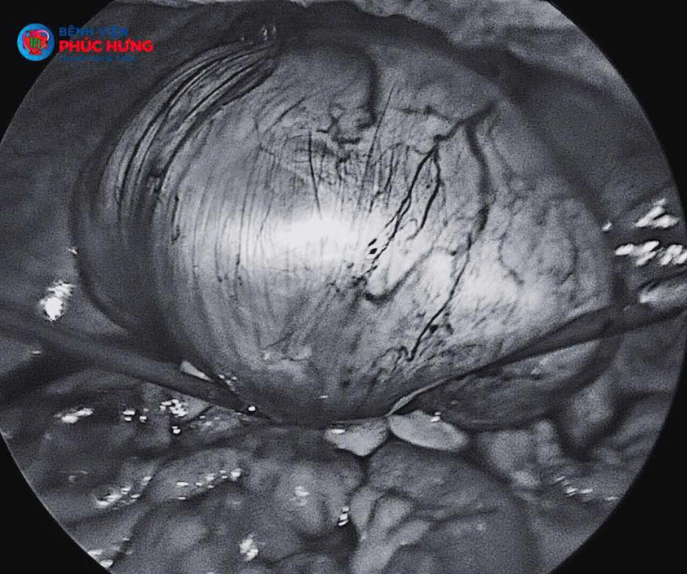

Bệnh nhân nhập viện trong tình trạng đau bụng dữ dội vùng hạ vị. Qua thăm khám lâm sàng, các bác sĩ phát hiện khối u lớn vượt lên trên rốn, chiếm gần 1/2 ổ bụng, ấn đau và di động kém. Kết quả siêu âm cho thấy một khối u "khổng lồ" đang đe dọa sức khỏe bệnh nhân. Một cuộc mổ nội soi cấp cứu đã được chỉ định ngay lập tức để giải quyết triệt để nguồn cơn gây đau và phòng ngừa biến chứng vỡ u hoặc xoắn u.

• Kích thước quá lớn: Khối u chiếm trọn phẫu trường, gây khó khăn cho việc đưa dụng cụ nội soi vào và thao tác.

• Tình trạng dính phức tạp: Khối u đã dính chặt vào tử cung, trực tràng và đại tràng xích ma.

Bằng kinh nghiệm dày dạn và sự khéo léo, ê-kíp bác sĩ đã tiến hành gỡ dính tỉ mỉ, bóc tách thành công khối u ra khỏi các cơ quan lân cận. Đặc biệt, các bác sĩ đã thực hiện cắt bảo tồn buồng trứng, giúp đảm bảo tối đa sức khỏe nội tiết cho bệnh nhân ở độ tuổi trung niên.